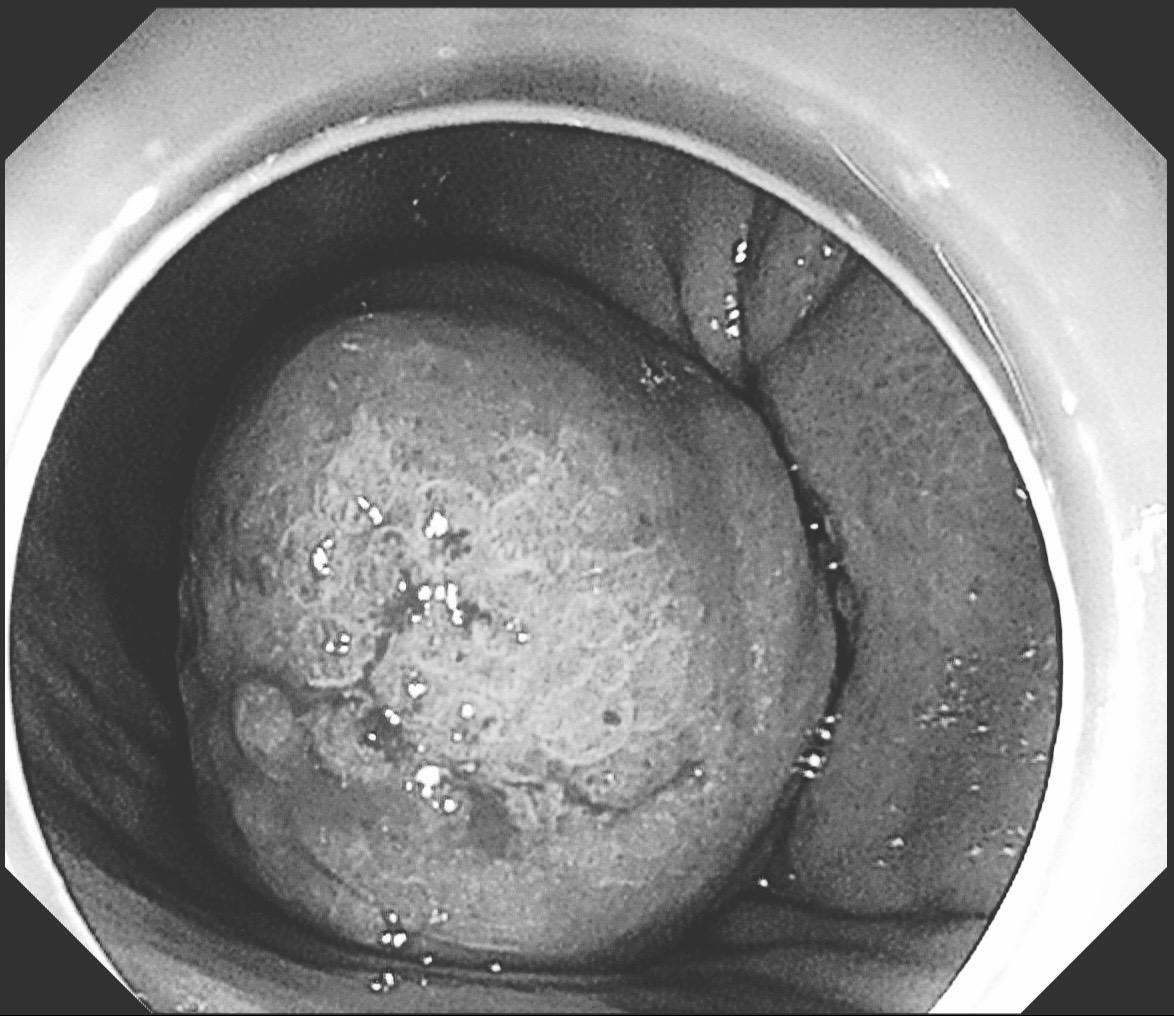

你性命相托,我必全力以赴。感谢信任!86岁,反复消化道出血1年多,血色素最低掉到6克。外科手术有可能保不住贲门,创伤大,家属拒绝。在外科老师备台、麻醉科的给力配合下,历时2个小时5厘米的瘤子完整切除并缝合。这种手术对患者是微创,对医生是巨创!